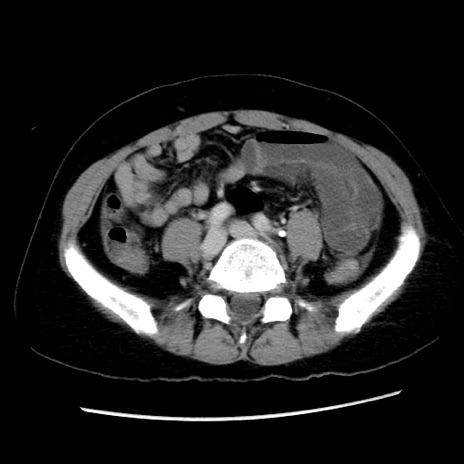

症例10(横断像)

【症例】 50歳代女性

【主訴】 腹痛

【現病歴】前日生レバーを食べた。今朝に排便あり。 昼前に突然発症の腹痛を生じ、当院救急外来を受診した。

【既往歴】 子宮筋腫にてで子宮全摘後

【身体所見】 意識清明、腹部:平坦、軟、下腹部やや左を中心に圧痛・反跳痛あり、筋性防御あり

【データ】WBC 7800、CRP 0.07